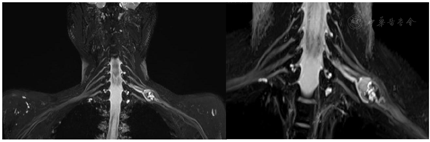

术前颈部MR平扫+增强(图1)与术前MRI-3D臂丛神经重建(图2)

术后查体:左肘腕关节活动自如,左臂屈曲、外展可,神经感觉未见明显异常。术后肿瘤组织送病理检查,HE染色示神经鞘瘤。免疫组化结果:S100(+),SMA(-)。术后2周后未出现臂丛神经损伤症状及其他并发症,治愈出院。术后1周(图3)、1个月(图4)、半年(图5)、一年(图6)复查颈部MRI+增强及臂丛神经重建如下。

对于臂丛神经鞘瘤,手术前明确诊断十分重要。由于缺乏典型的临床特征,该肿瘤的临床诊断较困难,即便是些专攻周围神经疾病的外科医生也常误诊为"肿大的淋巴结"。曾有学者等报道了2例癌症患者,在行PET-CT检查均发现在腋下或锁骨下区有高代谢的肿物,考虑为恶性肿瘤转移的淋巴结,然后行手术切除时术中才发现其来源于臂丛神经,从而考虑为臂丛神经鞘瘤[3]。除了常规的病史及体格检查外,MRI检查被认为是显示臂丛神经及其疾病较好的影像学检查方法[4]。术前常规MRI检查能清楚地显示肿瘤的部位、大小及其与臂丛神经的关系。T1加权像上肿物信号等于或略低于肌肉信号,T2加权像上肿物信号较高,可接近脑脊液信号。其注射增强剂后表现为中等度强化,但强化多不均匀。另外更进一步,本案例在常规MRI基础上对臂丛神经进行3D重建定位,使得肿瘤与臂丛神经的关系清晰可见,对于手术中神经保护有极其重要的参考价值。